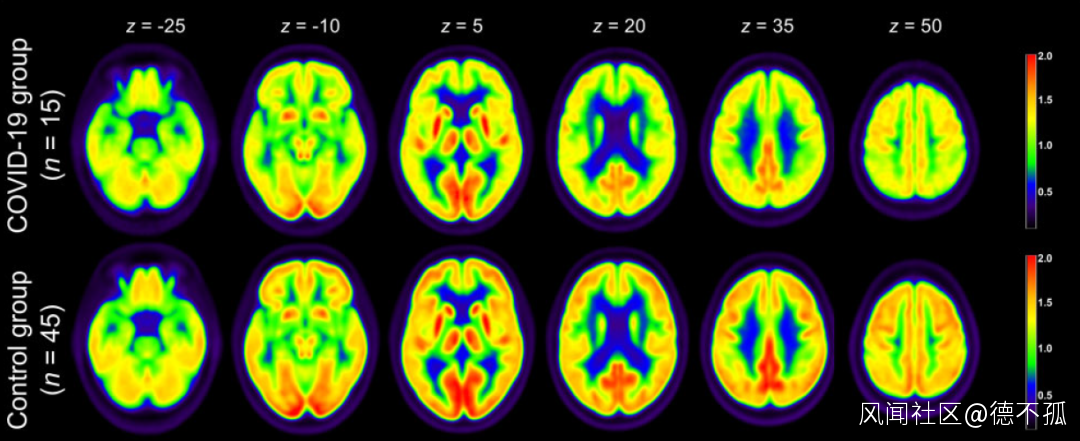

被新冠病毒感染後,部分患者的首發症狀表現為嗅覺、味覺減退或喪失等。這些感覺器官功能的改變其實反映的是中樞神經系統(腦)結構或者生理的變化。腦部成像可以清晰地記錄到這種變化,但是通過醫學影像學手段直接觀測新冠肺炎患者中樞神經系統變化的報道很少。德國弗萊堡大學醫學中心教授 Jonas A. Hosp 團隊通過對15名處於亞急性期且嗅覺和味覺出現異常的新冠肺炎患者的腦部進行PET(正電子發射型計算機斷層顯像,可通過檢測人體的代謝水平判斷疾病的發生發展)成像分析後發現,有10名患者的額頂葉位置出現代謝水平下降的現象 [1]。

圖1通過PET檢測新冠肺炎患者的腦部代謝變化**|** 圖源[1]